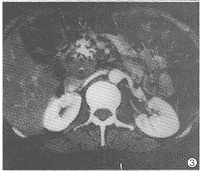

12例CT扫描均见胰腺实质内肿块形成。11例肿块位于胰头部,1例位于胰体部。6例为类圆形,直径为2.5~3cm,4例直径3.5~4cm,边缘规则,较均质,平扫CT值40~60HU,强化后70~110HU,与胰腺实质类似(图1)。2例直径大于4cm,密度不均,内见液化坏死灶,边缘不规则(图2)。8例见肿块内钙化(图3)。7例肿块B超表现为低回声,5例为不均匀回声。

图3 胰头部肿块内散在钙化